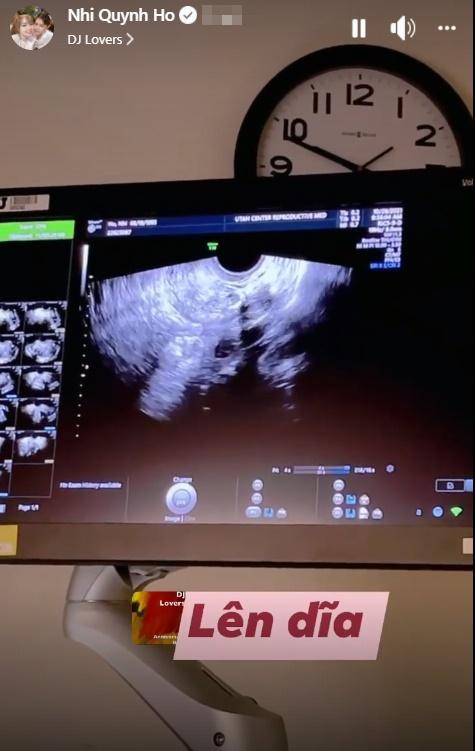

Múi Xù khoe ảnh siêu âm.

Cách đây vài ngày, Múi Xù gây chú ý khi khoe hình ảnh siêu âm. Qua chia sẻ có thể thấy hình ảnh thai nhi vẫn chưa được rõ nét. Nhưng trò chuyện với bạn bè, Bi Bảo đã tiết lộ về giới tính thai nhi.

"Gái đầu trai sau rồi", tomboy đình đám cộng đồng LGBT trả lời khi một người bạn vào giao kèo: "Nếu con trai thì tao tút tát cho con gái tao lên để cua nè".